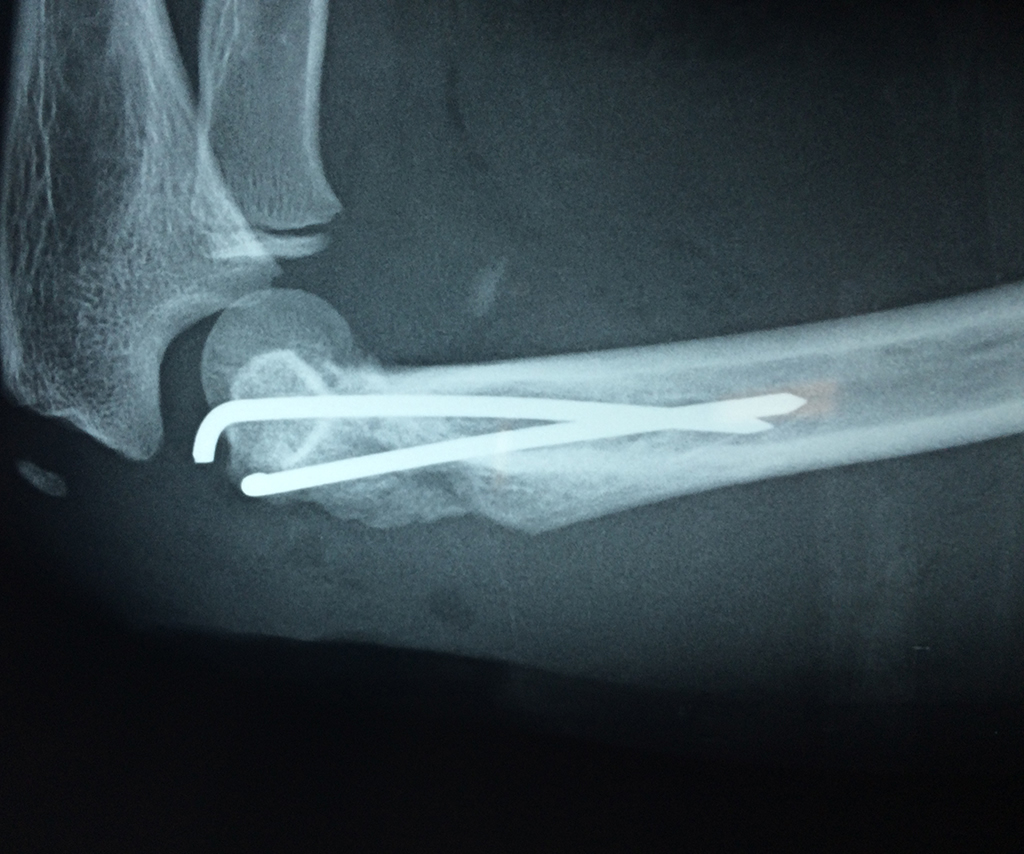

Cirugías de Calcaneo - Codo